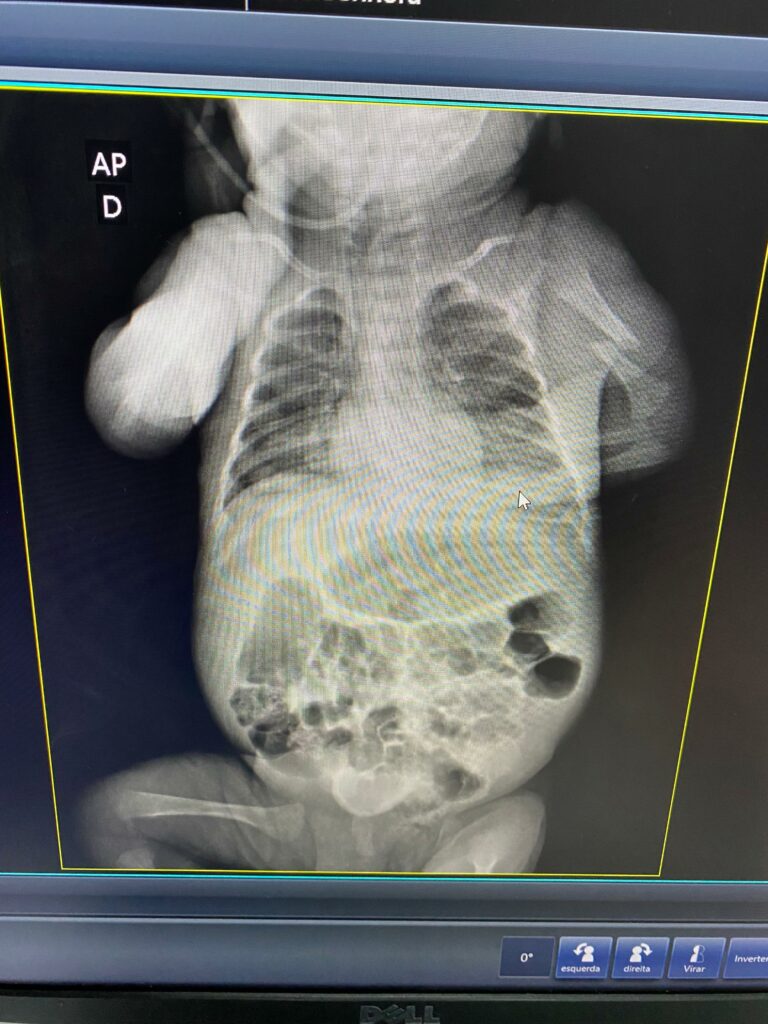

Segundo Lucas, a recém-nascida teria saído da UTI, com uma fissura no braço e a maternidade não teria dado nenhuma explicação sobre o motivo da situação, o deixando completamente indignado.

Ainda segundo ele, inconformado, procurou a assistente social do hospital, bem como a direção, para saber o motivo da bebê ter aparecido com braço enfaixado, visto que quando a mãe a deixou no local ela estava com os braços normais, mas não obteve nenhuma informação.

O Portal e T V CM7 Brasil deixa o espaço aberto para a manifestação da direção da Maternidade Balbina Mestrinho sobre o caso. Os pais da recém-nascida entregaram a equipe de reportagem todos os exames e documentos referente a internação e procedimentos realizados para respaldo, que não serão divulgados pela privacidade dos dados pessoais.

Os pais da bebê realizaram um boletim de ocorrência na Delegacia Especializada em Proteção à Criança e ao Adolescente (Depca) e um exame de corpo e delito foi solicitado pelo Instituto Médico Legal (IML), que foi realizado nesta quarta-feira (11).